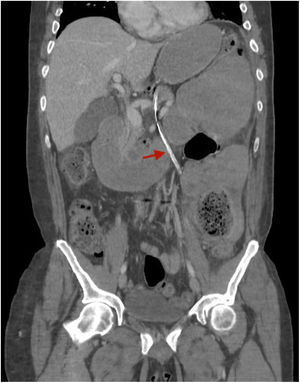

The patient is a 46-year-old male with a history of multiple abdominal surgeries who was admitted for intestinal obstruction. A nasogastric tube (NGT) was inserted, which was initially not productive. Due to clinical worsening, a thoracoabdominal computed tomography (CT) scan was requested, which revealed the extraluminal pathway of the NGT in the abdomen and thorax (Fig. 1); however, no perforation point was observed, and the perforation point was suspected at the cervical level (Fig. 2). ENT examination identified the perforation in the inferior cavum, dissecting the posterior wall of the pharynx. The NGT was withdrawn, and medical treatment was initiated with corticosteroids, fluconazole, and meropenem. The patient presented radiological clinical improvement and began oral tolerance after one week.